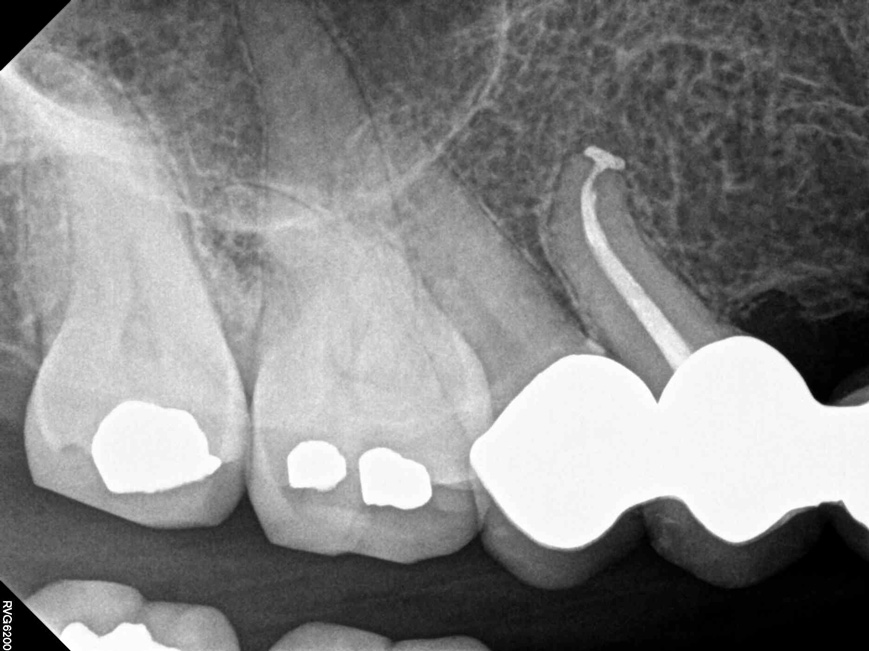

Fig 6.  Due to reported allergies to resin-based materials and eugenol, obturation was completed with a calcium hydroxide-based sealer (Figure 4 and Figure 5) with healing noted at a 1-year follow-up (Figure 6).

Figure 6

Fig 7. Cases treated by the continuous wave of condensation technique using gutta percha and epoxy resin sealer.

Figure 7

Fig 8. Cases treated by the continuous wave of condensation technique using gutta percha and epoxy resin sealer.

Figure 8